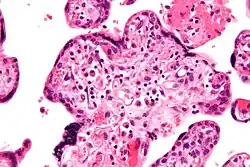

VUE does not have specific clinical signs and symptoms suggesting diagnosis; but an analysis of the inflammatory filtrate can aid in diagnosis.[1] The composition of inflammatory infiltrate in VUE on a cellular level is primarily macrophages and lymphocytes. The relative proportions of cells vary case by case. The lymphocytes present in VUE are predominantly CD8+ T-cells then CD4. There is usually a ratio of 0.1 to 0.5 for CD4/CD8.[17][18] The macrophages present are mainly Mac387-, followed by CD68 and HAM56+. Class 2 major histocompatibility complex (MHC) antigens on macrophages are up-regulated at sites of VUE. Neutrophils should not be present at sites of VUE. VUE is a condition involving inflammation and not infection. High numbers of neutrophils are present in infectious villitis and not VUE.[1][14]

Histomorphologically, VUE is characterized by a lymphocytic infiltrate of the chorionic villi without a demonstrable cause. Plasma cells should be absent; the presence of plasma cells suggests an infective etiology, e.g. CMV infection.

High mag.